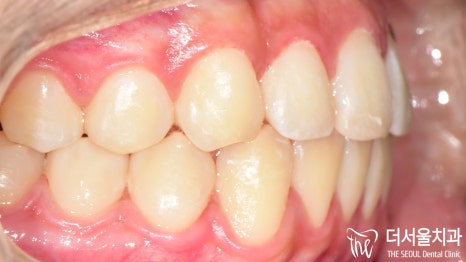

전과는 달리 벌어졌던 이 사이도

긴밀하게 붙어 있는 것이 확인되었으며

툭 튀어나와 있던 돌출입도 개선이 되었습니다.